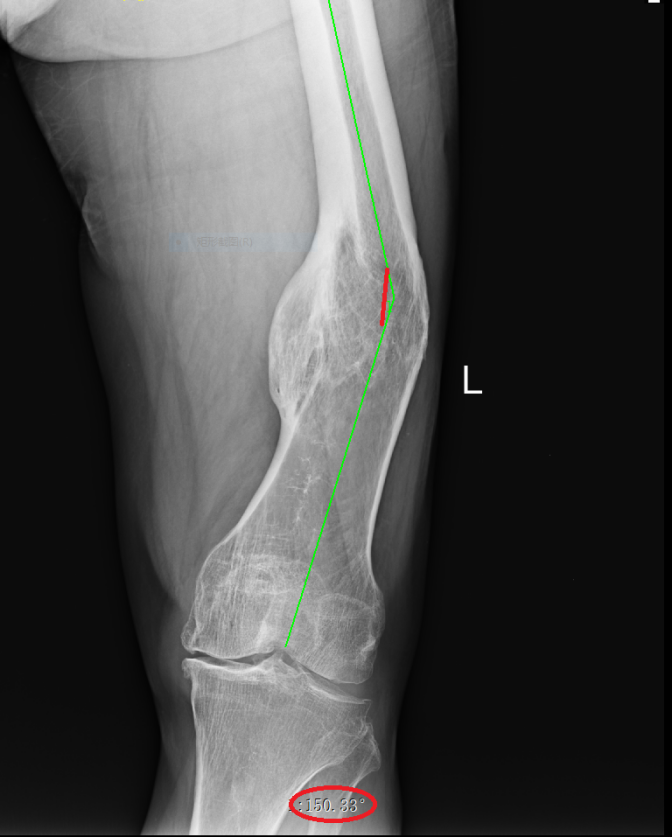

武明鑫教授為其仔細(xì)體格檢查,發(fā)現(xiàn)患者左大腿中下段外側(cè)可見一處12cm陳舊性切口疤痕,膝關(guān)節(jié)內(nèi)翻畸形,大腿中下段向外成角,膝關(guān)節(jié)內(nèi)外側(cè)局部壓痛,內(nèi)側(cè)尤為明顯,未觸及骨擦感及反?;顒?,肌力Ⅳ級,肌張力降低,左下肢較右下肢縮短約5.0厘米。拍X射線片檢查示:1.左股骨中下段骨質(zhì)膨隆并股骨彎曲,考慮是左股骨中下段骨折畸形愈合。2.左側(cè)膝關(guān)節(jié)退行性變。

術(shù)前X線片(內(nèi)翻成角30°)

術(shù)前X線片(向后成角17°)